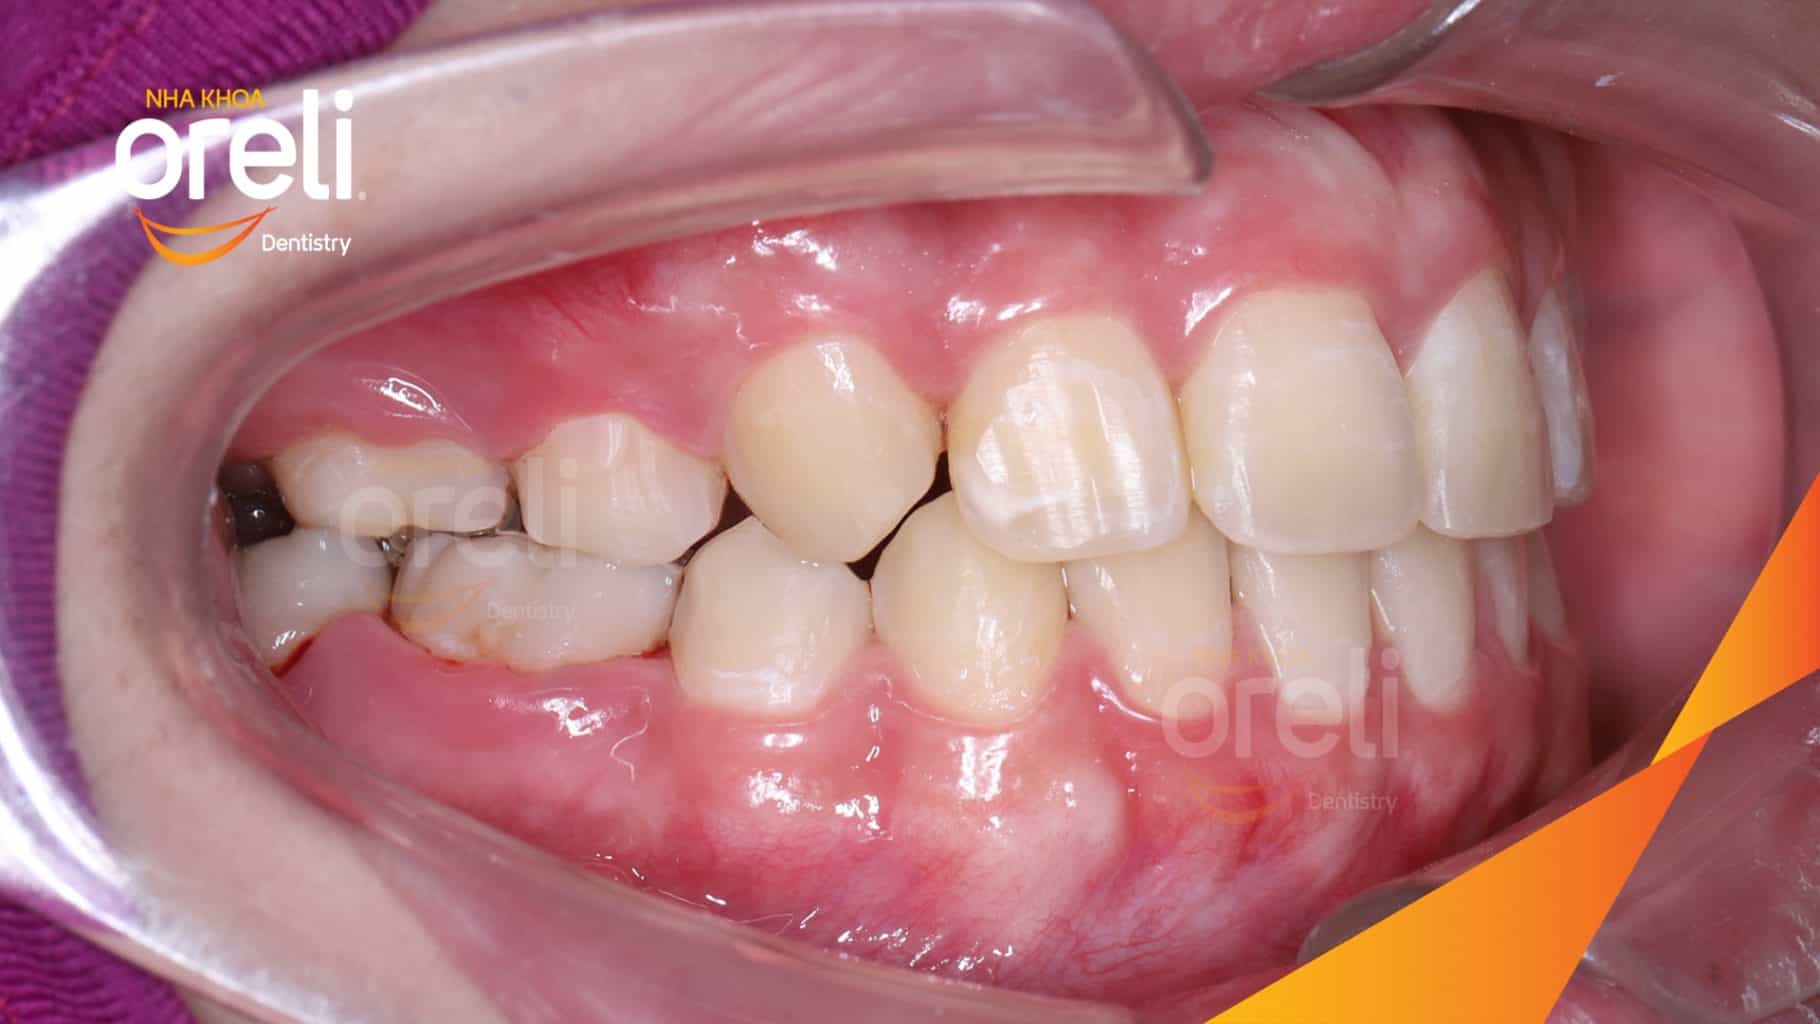

Tình trạng: Nhô xương ổ, trục răng nghiêng trước hai hàm, độ nhô môi nhiều

Giải pháp: Nhổ răng 4 chỉnh hô

Kết quả: Nụ cười hài hòa, mặt nghiêng đẹp, trục răng cửa đứng